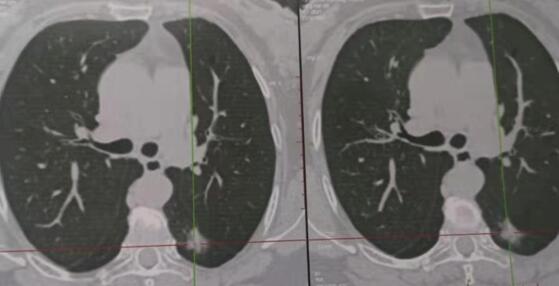

近日,腫瘤胸外科成功完成三例胸腔鏡下肺癌根治術。三名患者均系體檢時發現肺部直徑約15mm左右結節,行多項檢查均考慮惡性不除外,但無法確診,來我科就診,根據患者病情,苗滿園主任帶領科室醫師經研究討論,在全麻下行胸腔鏡下肺楔形切除送術中冰凍病理確診為肺癌,并行胸腔鏡下肺癌根治術,手術順利完成,時間2小時。科室全程引入加速康復理念,少插管,早拔管,患者均快速、順利康復出院。該治療的成功引入,使我院腫瘤胸外科胸腔鏡手術水平躍上新臺階。

傳統手術與微創手術的對比